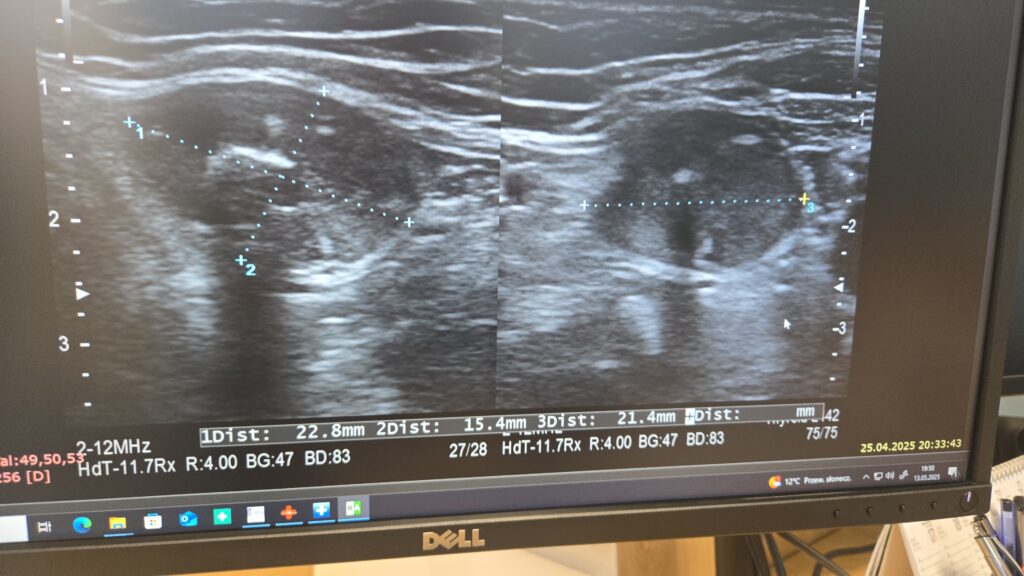

Podczas wizyty pacjent zostaje poproszony o położenie się na leżance i odchylenie głowy. Lekarz przykłada głowicę do skóry szyi, wcześniej pokrytej żelem, i analizuje obraz wyświetlany na monitorze. Cała procedura trwa kilkanaście minut i nie powoduje żadnego dyskomfortu.

W trakcie oceny lekarz analizuje:

- wielkość i kształt gruczołu,

- strukturę miąższu i ewentualne nieprawidłowości,

- obecność guzków, torbieli, zwapnień,

- unaczynienie tarczycy,

- stan okolicznych węzłów chłonnych.